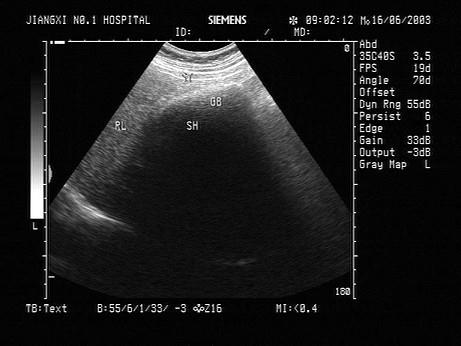

问题 男,64岁,右上腹反复疼痛不适数10年,加重5天。声像图如图所示,诊断为?(?)

选项 A.肝内钙化带 B.胆囊充满型结石并萎缩性胆囊炎 C.胆囊蛔虫 D.肠襻回声 E.胆囊癌

答案 B